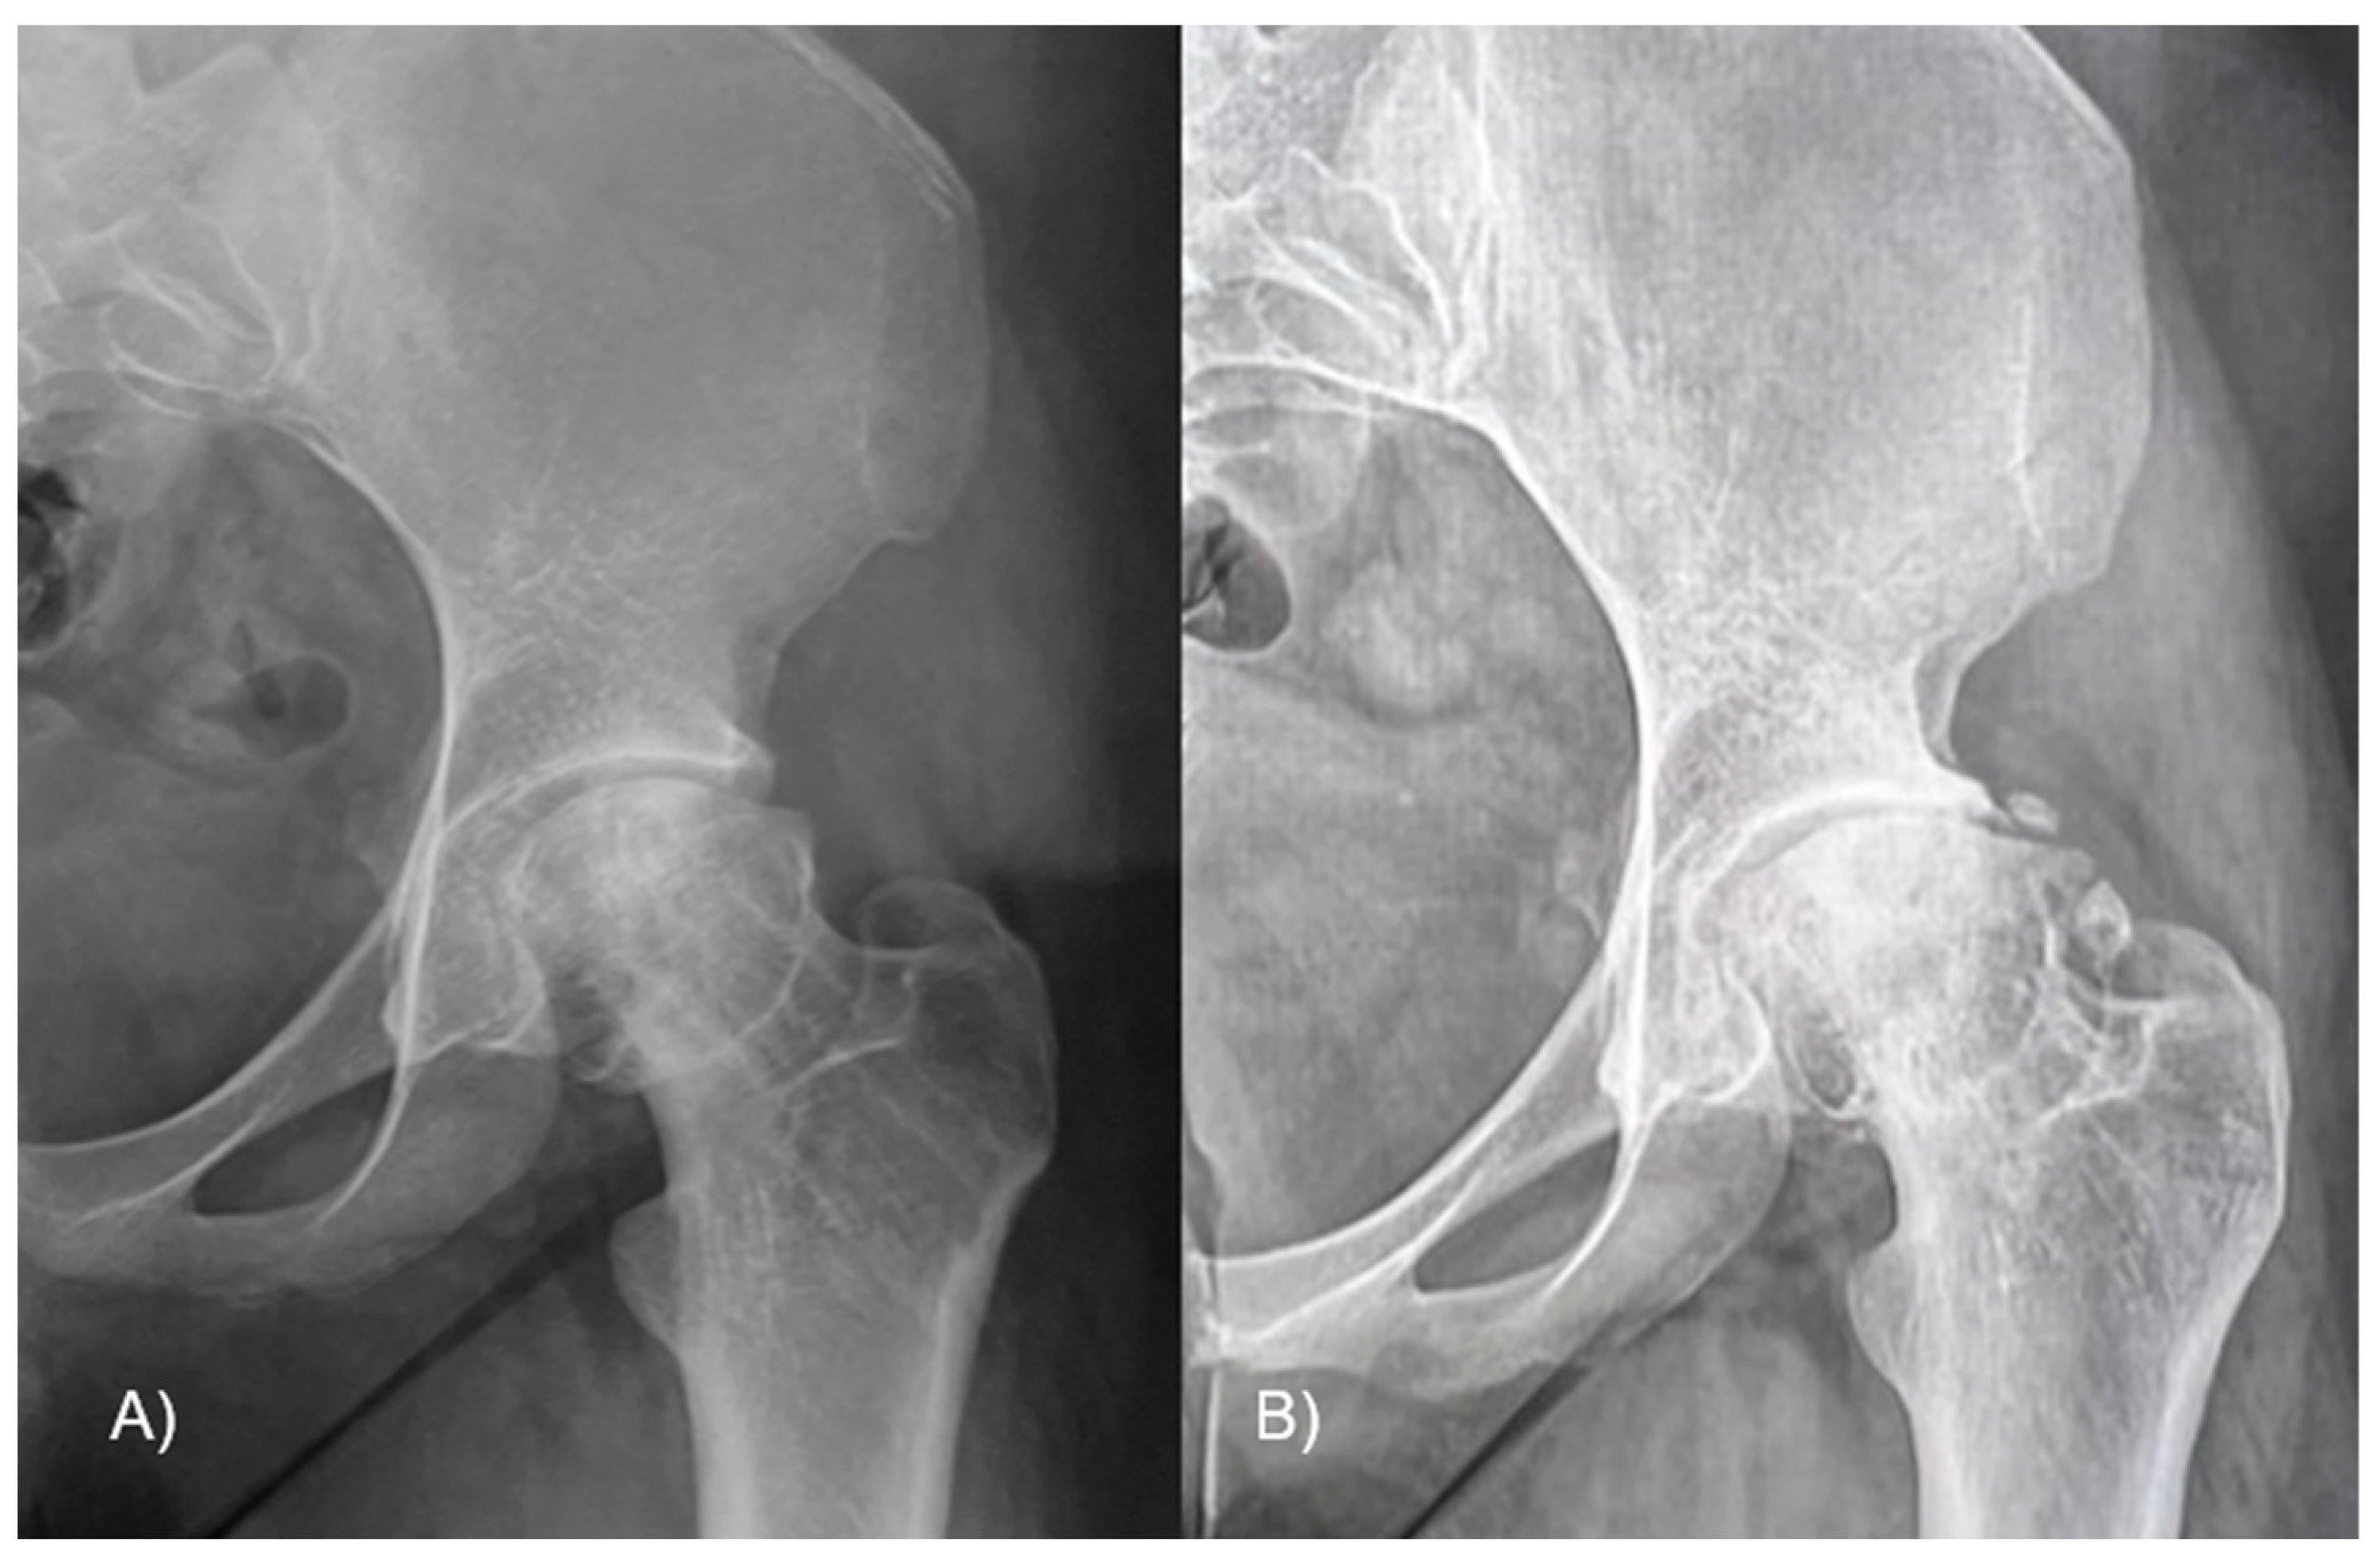

To evaluate the hip function, we used the Harris Hip Score (HHS) and hip joint articulation in the pre-operative period and at 3 and 6 months and 1 and 8 years follow-up. Anteroposterior and frog-leg lateral X-ray views were taken preoperatively and then at 4 weeks, 6 months, and yearly after. The level of slippage [24] was recorded in the pre-operative period and at last follow-up (Figure 3). The lateral α angle [25] and the epiphyseal–metaphyseal offset [26] were also evaluated preoperatively and at the latest follow-up.

Figure 3.

A 12-year-old male patient affected by SCFE, with great deformity of the proximal femur, with a varus (A) and retroverted (B) neck. The femur after the surgery, with the correction in the coronal (C) and sagittal planes (D); the screws in both views are in the bone and not protrude into the joint. The final X-ray follow-up at 8 years shows the outcome of removing screws and the radiological good hip joint status (E).